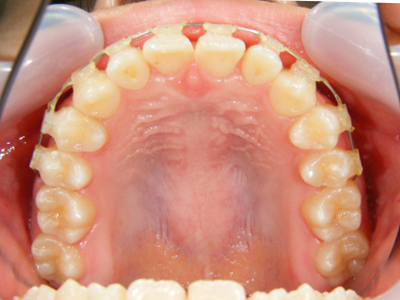

2. 術前上顎

上顎面観でやはり1,1番の翼状捻転および3,3番の捻転が著名。2次成長期を迎える患者様において、上顎歯列弓は劣成長と思われます。